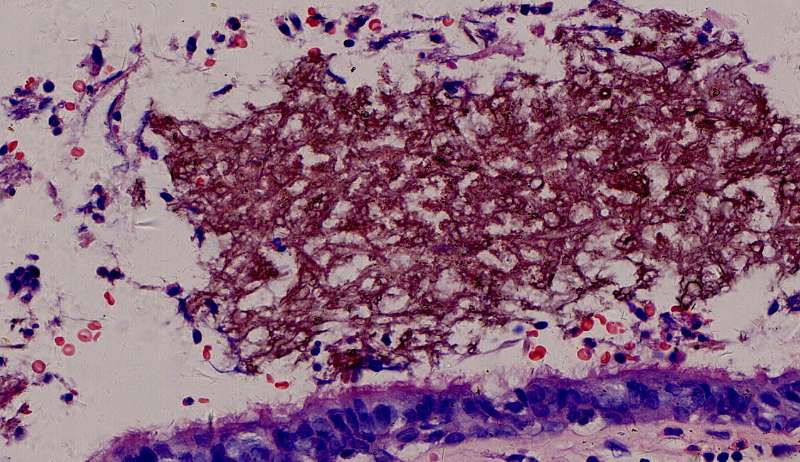

为什么有含铁血黄素呢? 曲霉菌容易使周围出现出血。太多含铁血黄素,吞不完 剩下一点曲霉菌,看看:

菌丝都快死了,隐约可见 这些红黑色点点是什么? 王:中性粒细胞,挺多的。这也是曲霉菌感染的一个特点。

曲霉菌孢子很少见到,基本都是菌丝团,这里也是支气管扩张区,菌丝团偏黄褐色,也快死了。

这里的菌丝形态清楚,下图小圆空的结构挺多,我理解为管状菌丝的断面

3rd 在隔离肺的支气管里 也是在扩张的支气管内,有炎症细胞 紫红的可能是锰铁化,曲霉菌能吸收空气中的锰铁元素,在周边